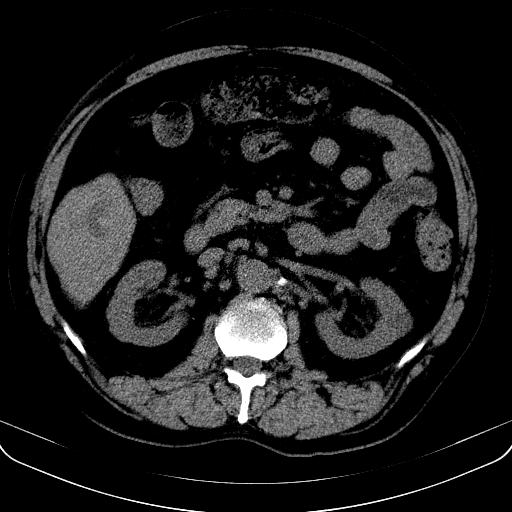

以下是引用jia119在2008-3-5 13:31:00的发言:[br]肝内多发片状低密度影,密度不均,我还是考虑肝ca可能,另肝内小囊肿,胆囊增大。

以下是引用形影不离在2008-3-5 12:18:00的发言:[br]肝硬化伴门脉高压征,肝内占位待排,增强再说.

以下是引用随光逐影在2008-3-5 21:11:00的发言:[br]肝硬化伴门脉高压(食管下段静脉曲张),肝癌不排除。建议:行ct增强扫描检查。

以下是引用同在2008-3-5 13:56:00的发言:[br]考虑肝癌可能性大,胆囊增大.